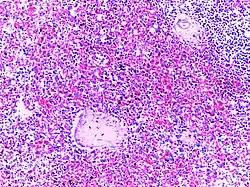

Hodgkin's lymphoma | Micrograph of a lymph node in Hodgkin's lymphoma with the characteristic Reed-Sternberg cell. RS cell is a large cell with abundant amophophilic cytoplasm and binucleate mirror image nuclei. Each nucleus contains an acidophilic nucleolus surrounded by a halo. | Category: Histopathology of Hodgkin's lymphoma | Hodgkin's lymphoma |

Dysgerminoma | Dysgerminoma characterized by uniform cells resembling primordial germ cells separated by fibrous septa with lymphocytes. | Category: Histopathology of ovarian dysgerminoma | Ovarian dysgerminoma |